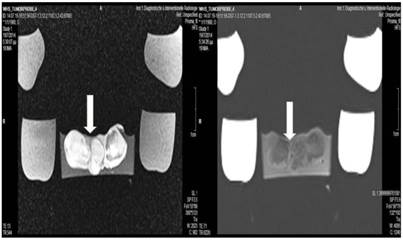

Figure 11

Lipiodol and microwave group; T1 sequence: Heterogeneous appearance with hypodensity sites indicating necrosis. T2 sequence: Heterogeneous appearance with hyperdensity sites indicating necrosis. White formations are lipiodol molecules entrapped within the tumor tissue.

Figure 12

Cisplatin and Microwave; T1 sequence: Heterogeneous appearance in the central part of the tumor, low intensity indicates necrosis. T2 sequence: High signal intensity indicates necrosis. White arrow indicates area where the microwave spike was inserted.

Tumor necrosis and apoptosis were the major purposes of our study. Survival was also recorded. Our records and MRI findings indicate that a major toxicity was observed in the group where cisplatin, lipiodol and microwave were applied. None of the animals survived more than a week. Moreover; hemorrhage apart from necrosis was observed inside the tumors. Survival was the following for the groups: microwave (25days) ≥ cisplatin (22 days) > control (20 days) > lipiodol (16 days)> microwave plus lipiodol (16 days) > cisplatin plus lipiodol (12) > cisplatin plus microwave (12 days) > lipiodol plus cisplatin plus microwave (5 days). (Figure 5-12.)